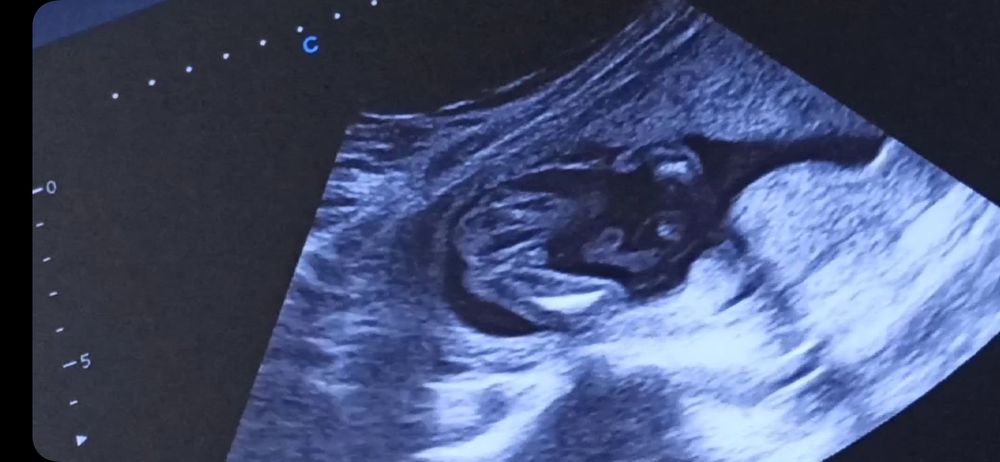

УЗИ в 17 неделек. Пол?

Пол малышаВопрос знатокам? Кто разбирается? Это мальчик или девочка?

Прикрепляю несколько противоречивых скринов с видео.

Врач очень не уверена предположила. Малыш крутился.

UPD. если девочка, на других скринах пуповина?

Татьянка, я так и делала. Это всё скрины с одного минутного видео. Уже поставила на замедленное воспроизведение, смотрела изучала. Весь инет перерыла сравнивала. Ну чисто 50/50)))) кума говорит, на девочку похожа, я думаю что похоже на мальчика, муж бредит девочкой и говорит мне, что у мальчиков мошонка должна быть и где она, её нет. Врач предположила мальчика. Но не уверенно.